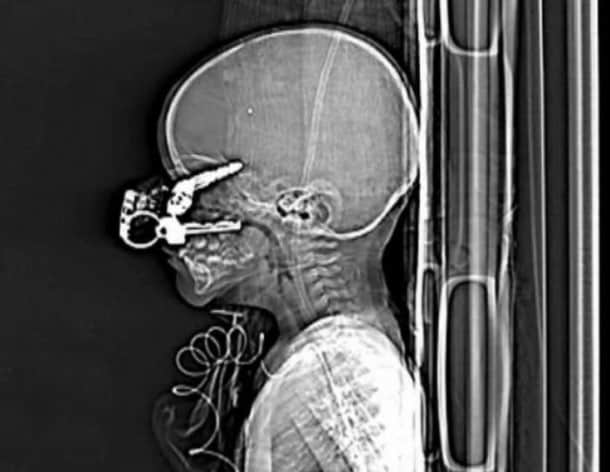

33 radiographies qui prouvent que les gens font des choses douteuses avec leur corps !